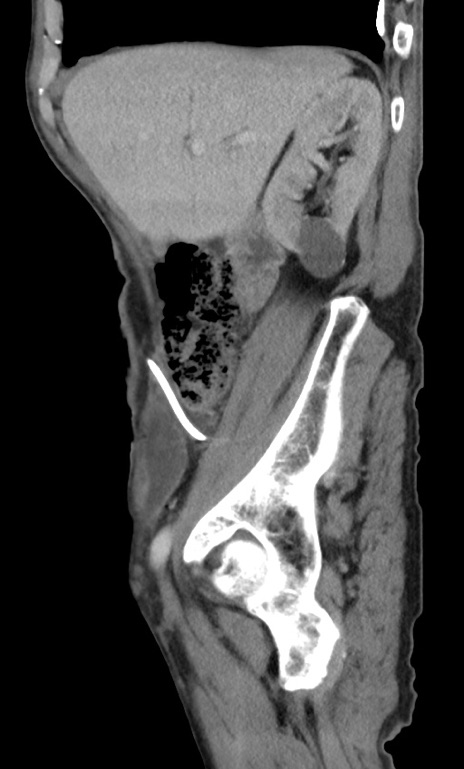

症例3(矢状断像)

【症例】 70歳代男性

【主訴】右鼠径部腫瘤、疼痛

【現病歴】本日朝より上記主訴あり、受診。

【既往歴】膀胱癌にて膀胱全摘、両側尿管皮膚瘻

【データ】WBC 5600、CRP 0.56